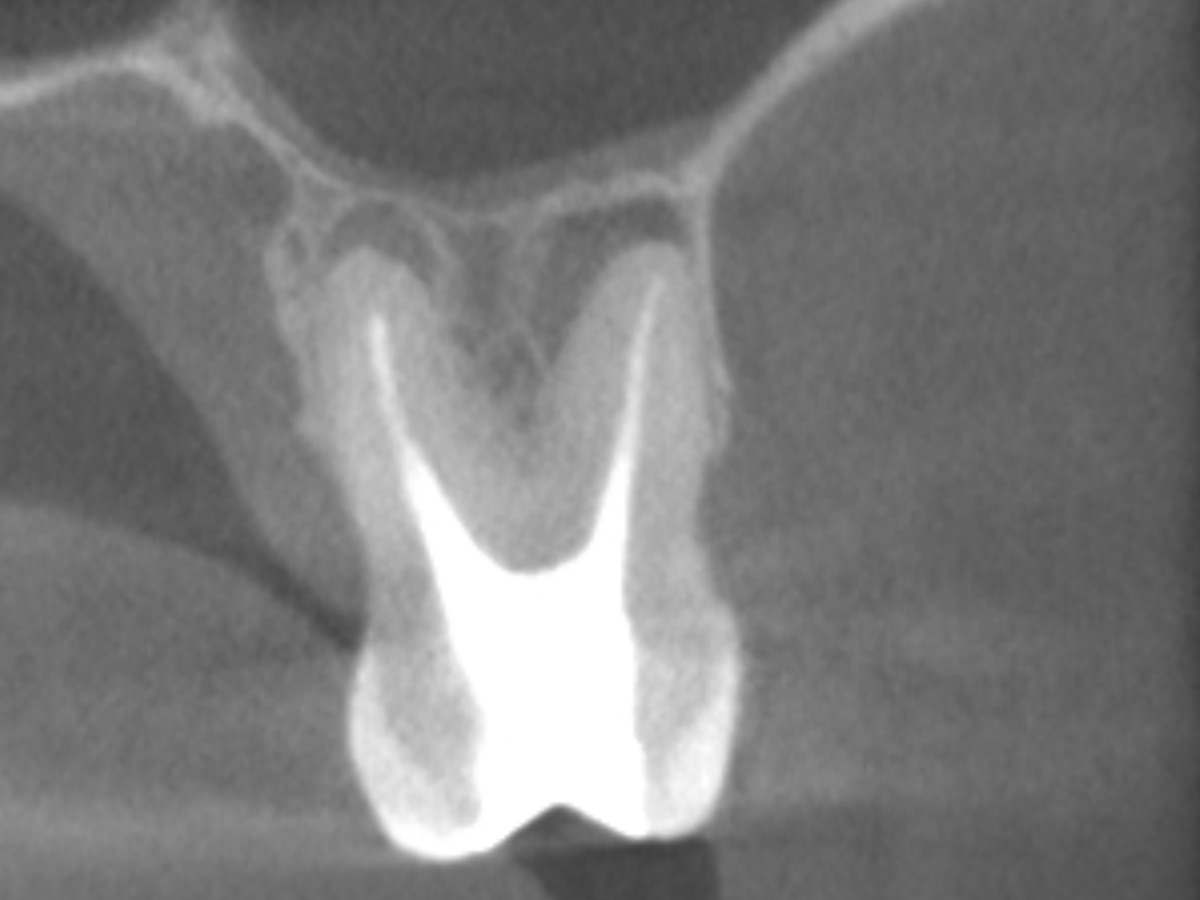

Obturation nach einer erfolgreichen Revision der insuffizienten Wurzelkanalfüllung mit einer symptomatischen apikalen Parodontitis

Der Patient stellte sich mit Aufbissschmerzen vor, wobei die klinische und röntgenologische Untersuchung eine symptomatische apikale Parodontitis an einem bereits wurzelkanalbehandelten Zahn 26 ergab. Die DVT-Aufnahme deutete auf einen unbehandelten zusätzlichen Kanal in der mesio-bukkalen Wurzel hin. Die Darstellung und Behandlung des mb2s sowie die Revision der bereits behandelten Kanäle erfolgte mit dem XP-endo® Rise Shaper bei einer hohen Umdrehungszahl von 2.500rpm.

Abbildung 2

DVT koronal